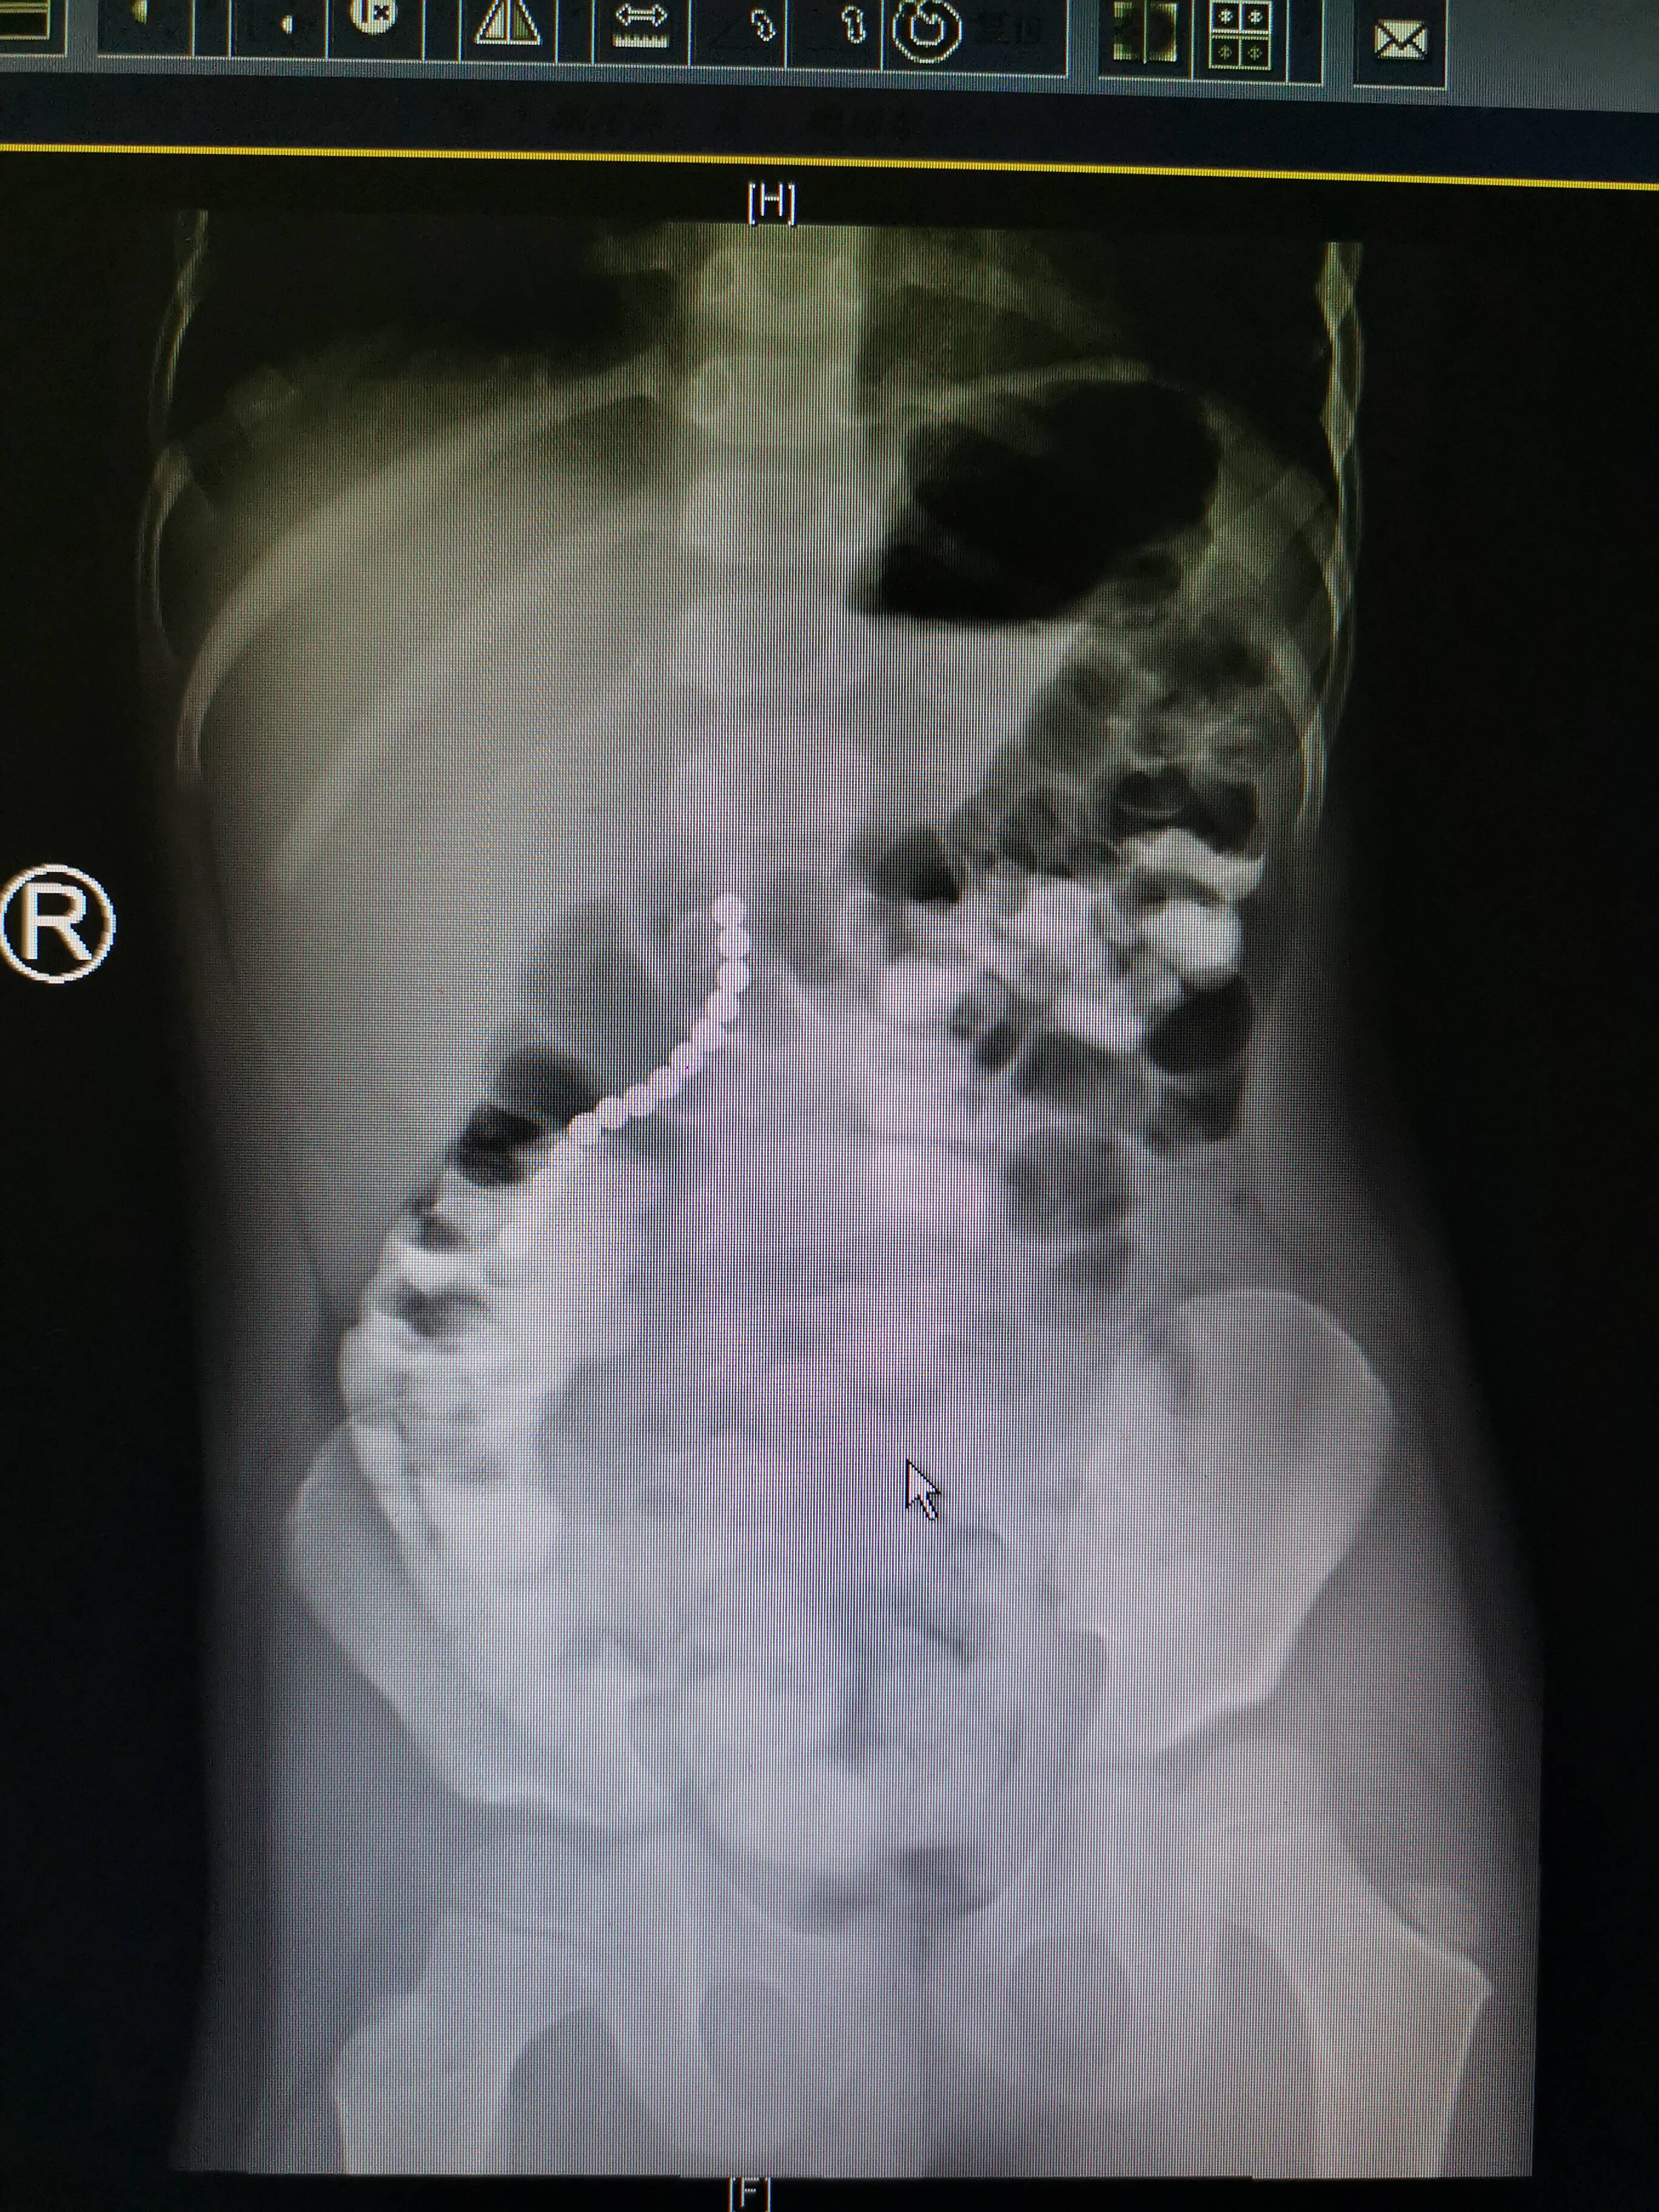

“看到孩子X光片上的影像,我们都惊呆了,14颗磁力珠在孩子的消化道里连成了一长串,就像是一条珍珠项链。”陈鑫讲述,8月31日,只有5岁的男孩亮亮(化名)突然喊肚子疼,刚开始父母并没有在意,只是给孩子喝了点热水,但很快发现孩子情况异常,出现呕吐、出虚汗等症状,父母这才意识到问题严重,再三追问亮亮才说出真相。“亮亮的哥哥有一套开发智力的玩具磁力珠,是价格比较贵的进口玩具,我们其实之前就担心被亮亮误吞,从来不让他玩,专门放到了亮亮接触不但的地方。”家长向陈鑫讲述意外发生的原因,但这次不知道亮亮怎么把高处的磁力珠拿了下来,还因为好奇吞下了很多。他们在网上查了类似的案例,吓出了一身冷汗,赶紧把孩子送到了青大附院小儿外科求助。

看到14颗磁力珠在孩子消化道里互相吸附连成一串,孩子除了偶尔腹痛、呕吐外没有其他症状,当时的接诊医生建议先留院观察一下,看练成一串的磁力珠能否被人体自然排出。但两天过去了,X光影像显示磁力珠的位置几乎没有变化,此时孩子的情况仍然比较正常,但陈鑫和同事们却认为,不能再等下去了。“X光影像只是二维的,无法判断磁力珠在孩子的胃里还是肠道里,CT检查受到磁力珠的影响,也无法准确定位,开腹探查是最后的探查手段。”陈鑫说,9月3日下午2时,亮亮被推进了手术室,小儿外科手术团队打开孩子的腹腔发现,情况比预计得更为严重。14颗磁力珠看起来连成了一串,但这只是一种误导医生的假象。磁力珠实际上分成3个部分,两颗磁力珠在胃里,7颗在小肠里,还有5颗在结肠里,但因为磁力珠的强磁性,哪怕隔着肠壁和胃壁仍然能牢牢地吸在一起,造成孩子的胃、小肠和结肠多处穿孔。当时这些孔洞被磁力珠完全封堵住,肠道气体都没有扩散到腹腔中,因此孩子并没有出现消化道穿孔的典型症状。